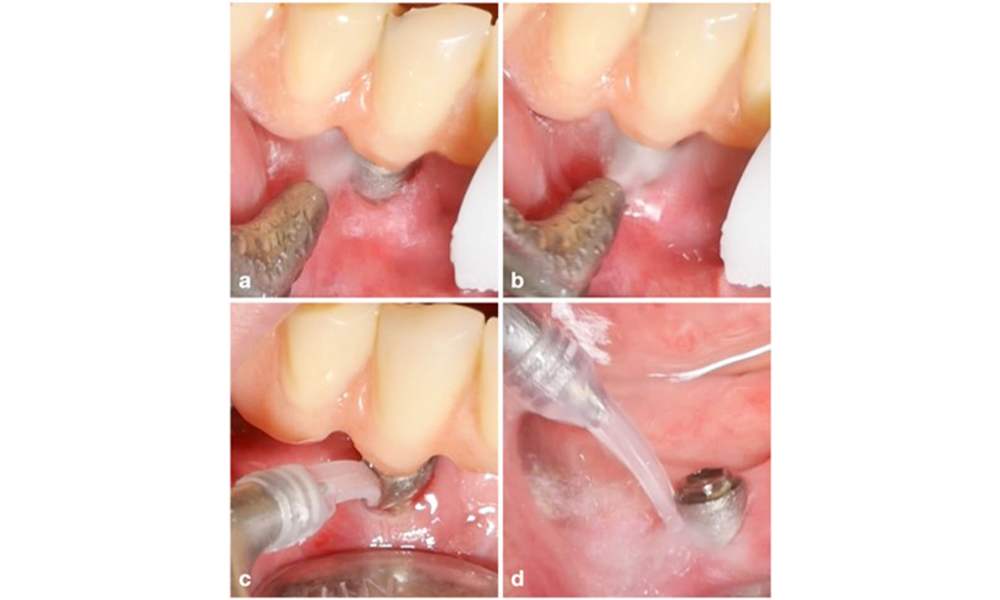

The World Workshop on the Classification of Periodontal and Peri‐Implant Diseases and Conditions from 2017 established diagnostic criteria for peri-implant mucositis and peri-implantitis (Renvert et al. 2018). Peri-implant mucositis is defined as (1) presence of inflammation around the implant (i.e., redness, swelling, line or drop of bleeding within 30 seconds of probing), combined with (2) no additional bone loss after initial healing (figure 1).

Implant in position 26 with peri-implant mucositis (a–c). The probing depth value of 5 mm (b) remains consistent with the measurement taken a few weeks after placing the prosthetic reconstruction. There is bleeding on probing (c) but the radiograph indicates no additional bone loss beyond what is expected for marginal bone remodelling (d).

Figure 1. Implant in position 26 with peri-implant mucositis (a–c). The probing depth value of 5 mm (b) remains consistent with the measurement taken a few weeks after placing the prosthetic reconstruction. There is bleeding on probing (c) but the radiograph indicates no additional bone loss beyond what is expected for marginal bone remodelling (d).